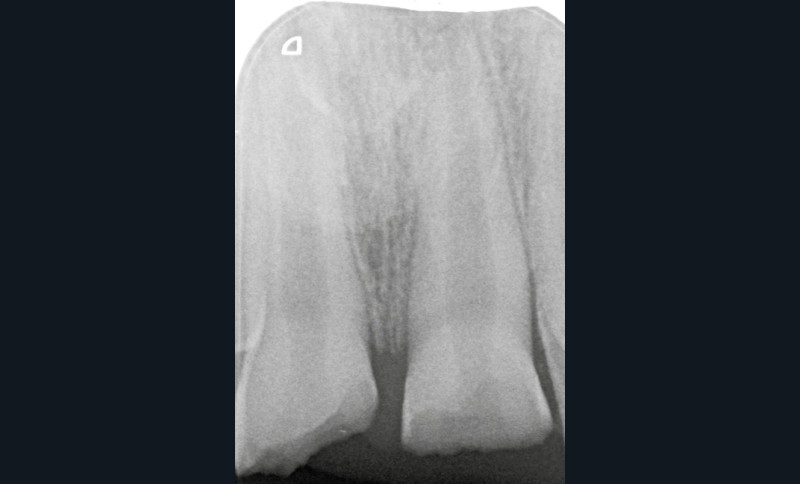

L’examen radiologique montre que les racines de 11 et 21 ne sont pas totalement édifiées (fig. 3). La priorité sera alors de conserver la vitalité pulpaire de ces dents immatures.